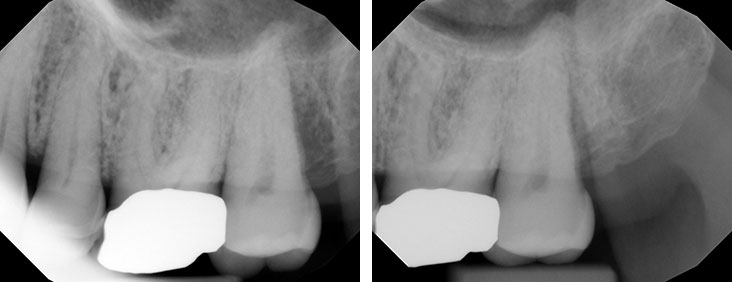

Before & After

Case by Dr. French